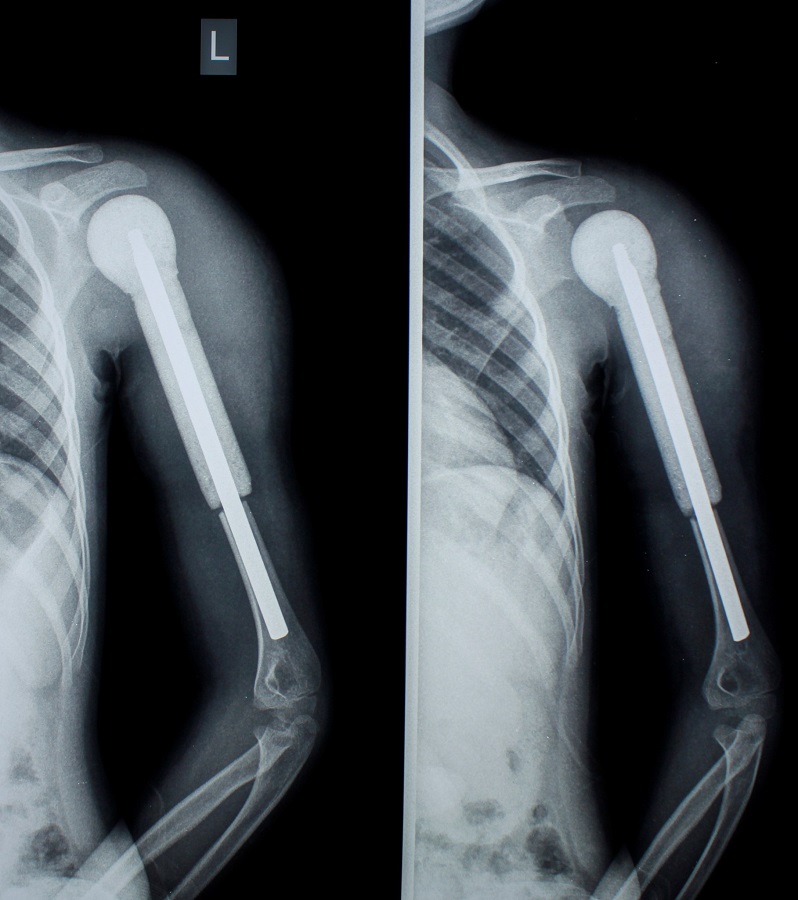

Բազկոսկրի Յուինգի սարկոմա (չարորակ) ունեցող 6-ամյա աղջնակի մոտ վիրահատական միջամտությունից հետո պահպանվել է վերին վերջույթը:

Երեխան նաև քիմիաթերապիայի 7 կուրս է անցել:

Վիրահատությունը Մանկական վնասվածքաբանության և օրթոպեդիայի կլինիկայի ղեկավար, «Մուրացան» ամալսարանական հիվանդանոցի գլխավոր բժշկի տեղակալ Արարատ Նազանյանը կատարել է «Նաիրի» բժշկական կենտրոնի ոսկրային օնկոլոգիայի կլինիկայի ղեկավար Գալուստ Գալստյանի հետ համատեղ: